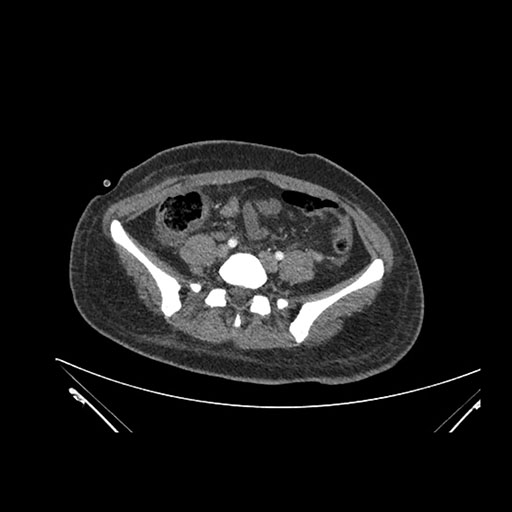

Imaging Analysis

Look through the patient's CT scan to identify any areas of concern for the necessary procedure.

Axial Venous